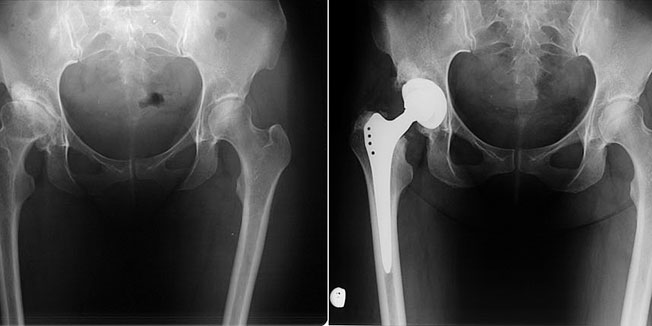

ZAGREB - Premda se već gotovo godinu i pol u Hrvatskoj ne ugrađuju kukovi ASR tvrtke DePuy, najnovija panika koja se oko tog proizvoda podigla u Velikoj Britaniji aktualizirala je pitanje sigurnosti pacijenata s takvim protezama i u Hrvatskoj.

Problem s tom vrstom potpuno metalnih proteza je u činjenici da se zbog jakog trenja metal ljušti pa u krv odlaze otrovne čestice poput kroma i kobalta. To može biti vrlo opasno za, primjerice, osobe koje su inače alergične na metale ili pak one koje imaju problema s bubrezima, a posebice za žene.

Prema podacima, u Velikoj Britaniji je oko 10.000 osoba kojima su ugrađeni sporni kukovi, dok hrvatske procjene govore o oko 325 pacijenata kojima je prije zabrane Hrvatske agencije za lijekove u kolovozu 2010. u ortopedsk...